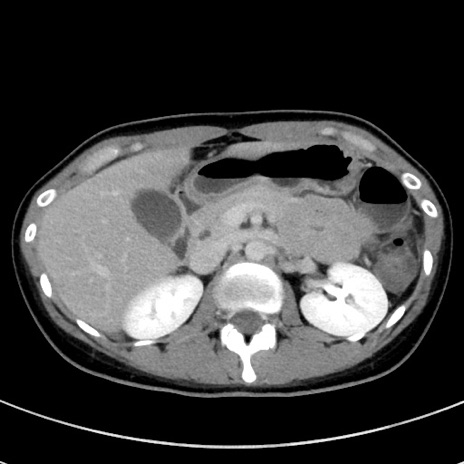

症例17(横断像)

【症例】20歳代女性

【主訴】嘔吐、下腹部痛

【現病歴】昨日夕食後に嘔吐し下腹部痛が出現。本日になっても嘔吐持続し改善しないため来院。

【身体所見】意識清明、BT 37.2℃、BP 108/67mmHg、腹部:平坦、やや硬、下腹部正中から右にかけて圧痛あり、反跳痛軽度あり、tapping pain(+)。

【データ】WBC 13600、CRP 14.94